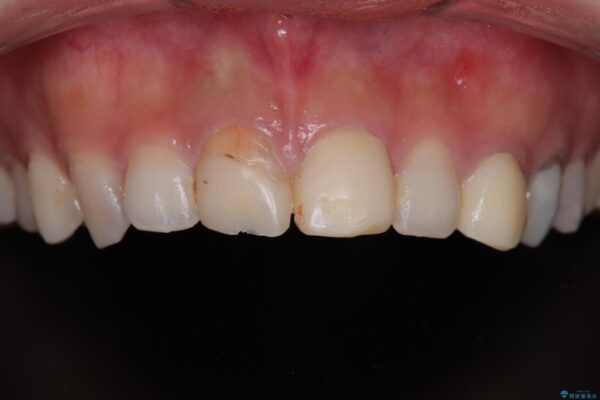

治療前

• 「抜歯してブリッジ」と言われた20代女性が選んだ治療とは|たった4か月で自然な笑顔に抜歯即時インプラント+審美補綴の症例 治療前画像

20代女性の患者様。 他院にて「上の前歯(右上中切歯)は抜歯してインプラントかブリッジにする必要がある」と診断され、大変ショックを受けられていました。 すでに根管治療を受けた歯でしたが、急に担当医が変わり、「抜歯が必要」とだけ説明されたことに不安感を抱き、当院を受診されました。 左上中切歯と犬歯も仮歯のままで、将来への不安が大きかったご様子です。